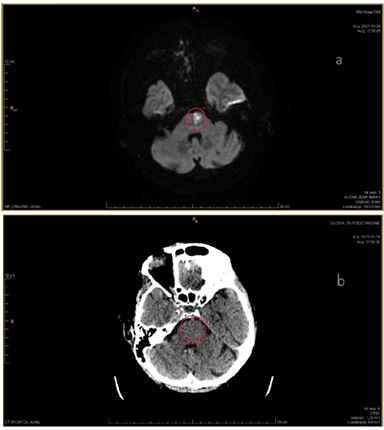

Dominika Oborska-KumaszyńskaCancer Centre London, 49 Parkside, Wimbledon, London SW19 5NB, Wielka Brytania; dominika.oborska-kumaszynska@cancercentrelondon.co.uk (D.O.-K.) Streszczenie Nowotwory głowy i szyi obejmują heterogenną grupę nowotworów wywodzących się z górnych dróg oddechowych i przewodu pokarmowego, zatok przynosowych oraz ślinianek i tarczycy. Optymalne postępowanie w leczeniu tych nowotworów wymaga multidyscyplinarnego podejścia. Radioterapia jest jedną z technik oferowanych w kompleksowym…